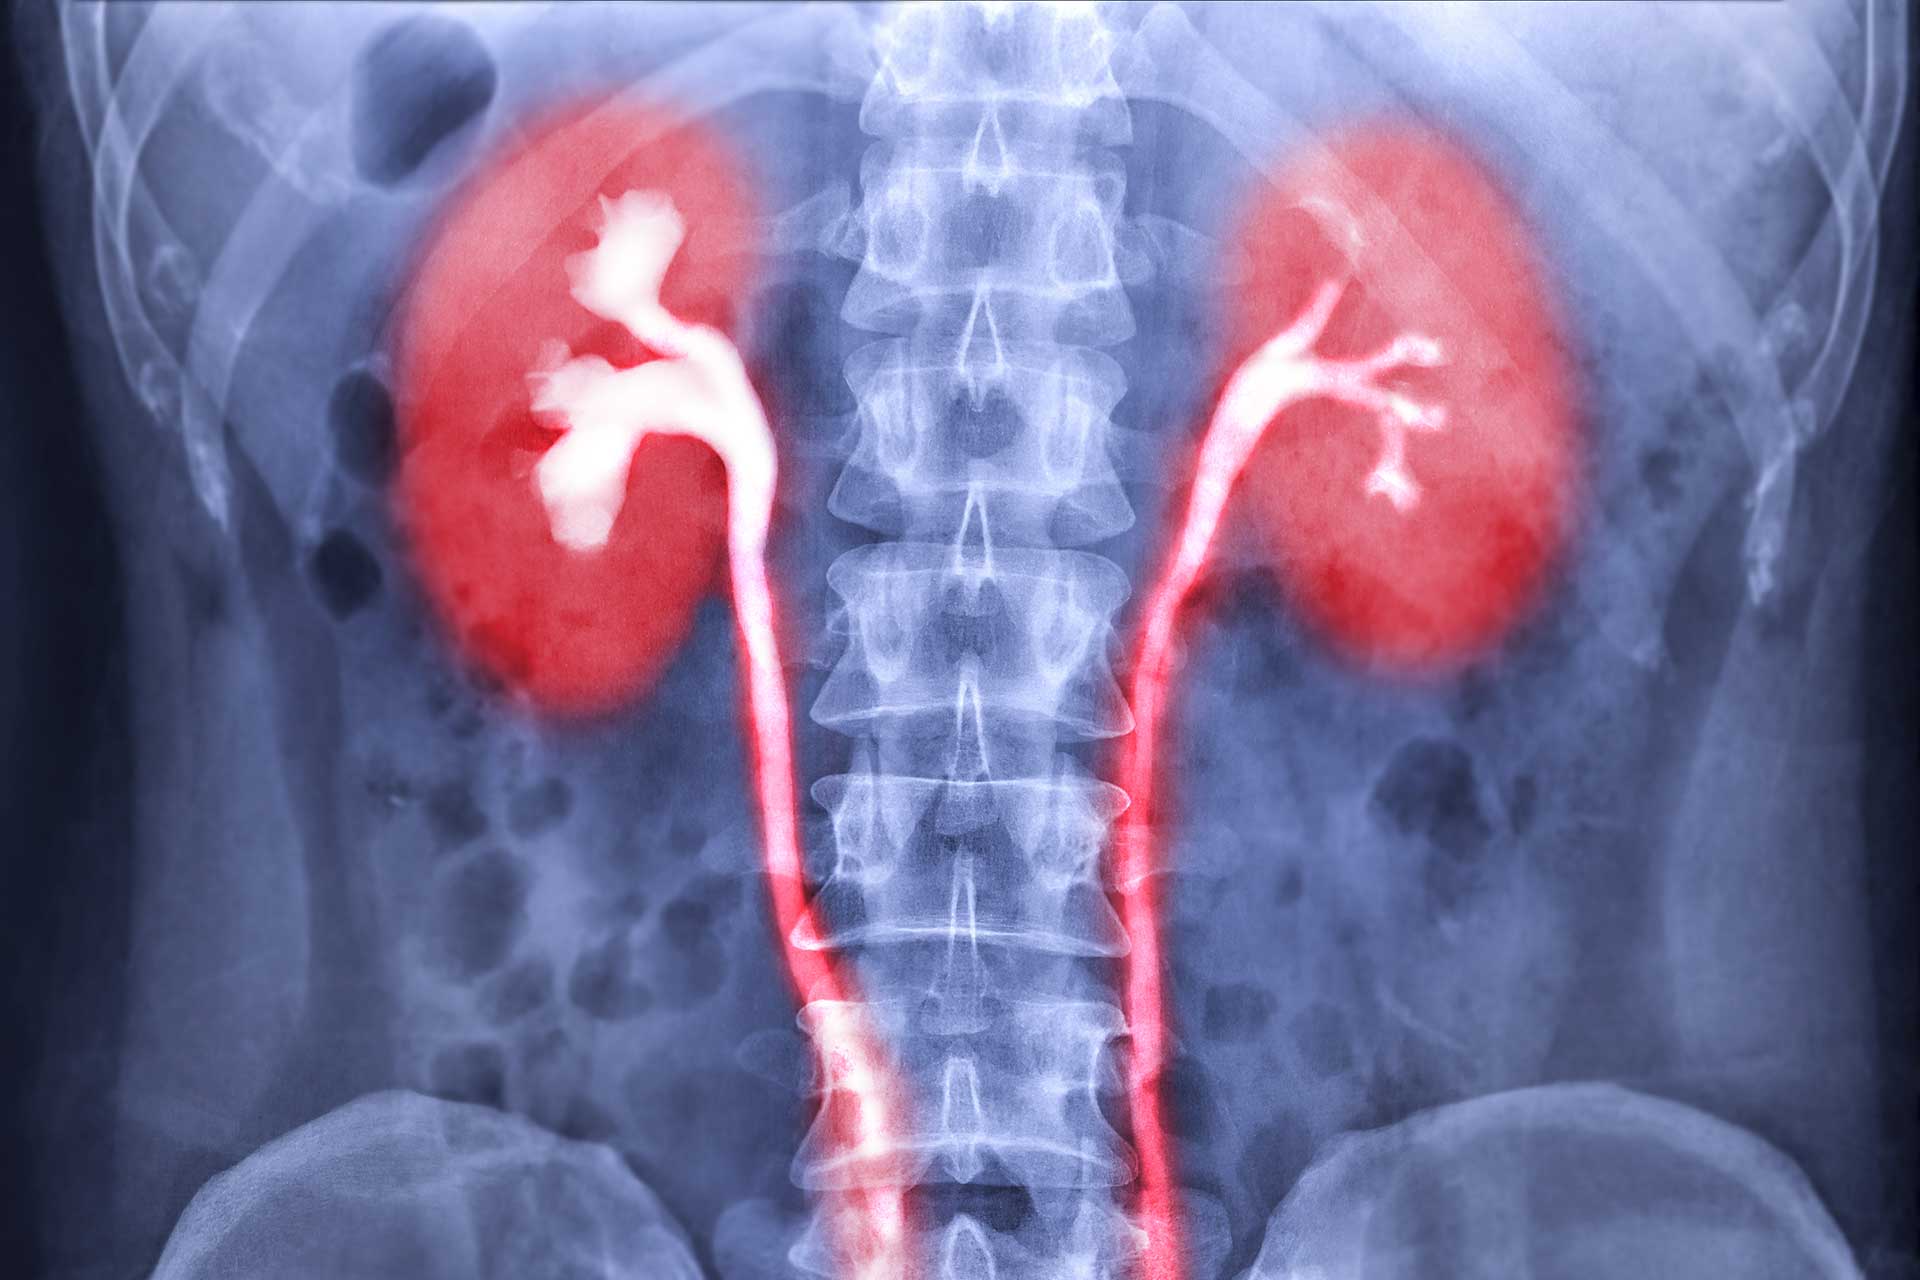

Durch Röntgenuntersuchungen in der Urologie kann entweder das gesamte ableitende Harnsystem oder ein spezieller Bereich untersucht werden. Die meisten urologischen Röntgenuntersuchungen werden mit Kontrastmittel durchgeführt.

- Infusionsurogramm

Diese Röntgenuntersuchung der Nieren, der Harnleiter und der Blase ermöglicht die Diagnostik von Tumoren des ableitenden Harnsystems, exakte Lokalisation und Darstellung von Steinen und Harnabflusstörungen. - Urethrogramm